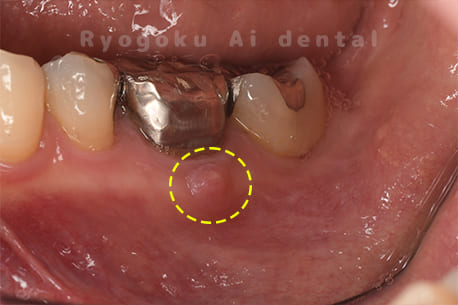

Case05

-

- 原因

- 慢性根尖性歯周炎

- 治療内容

- マイクロエンド

- 治療費用

- 121,000円(被せ物は含まない)

他院ではお薬の交換と抗生剤の処方で経過を診ていた患者さんです。歯茎の腫れが治らないとのことで、根管治療を開始し、2回目のご来院で腫れが引いたケースです。現在は被せ物も入り、良好に経過しております。

<リスク・副作用>

術後は痛み、腫れ、痺れなどの副作用が生じる場合があります。症状が再発する可能性があります。